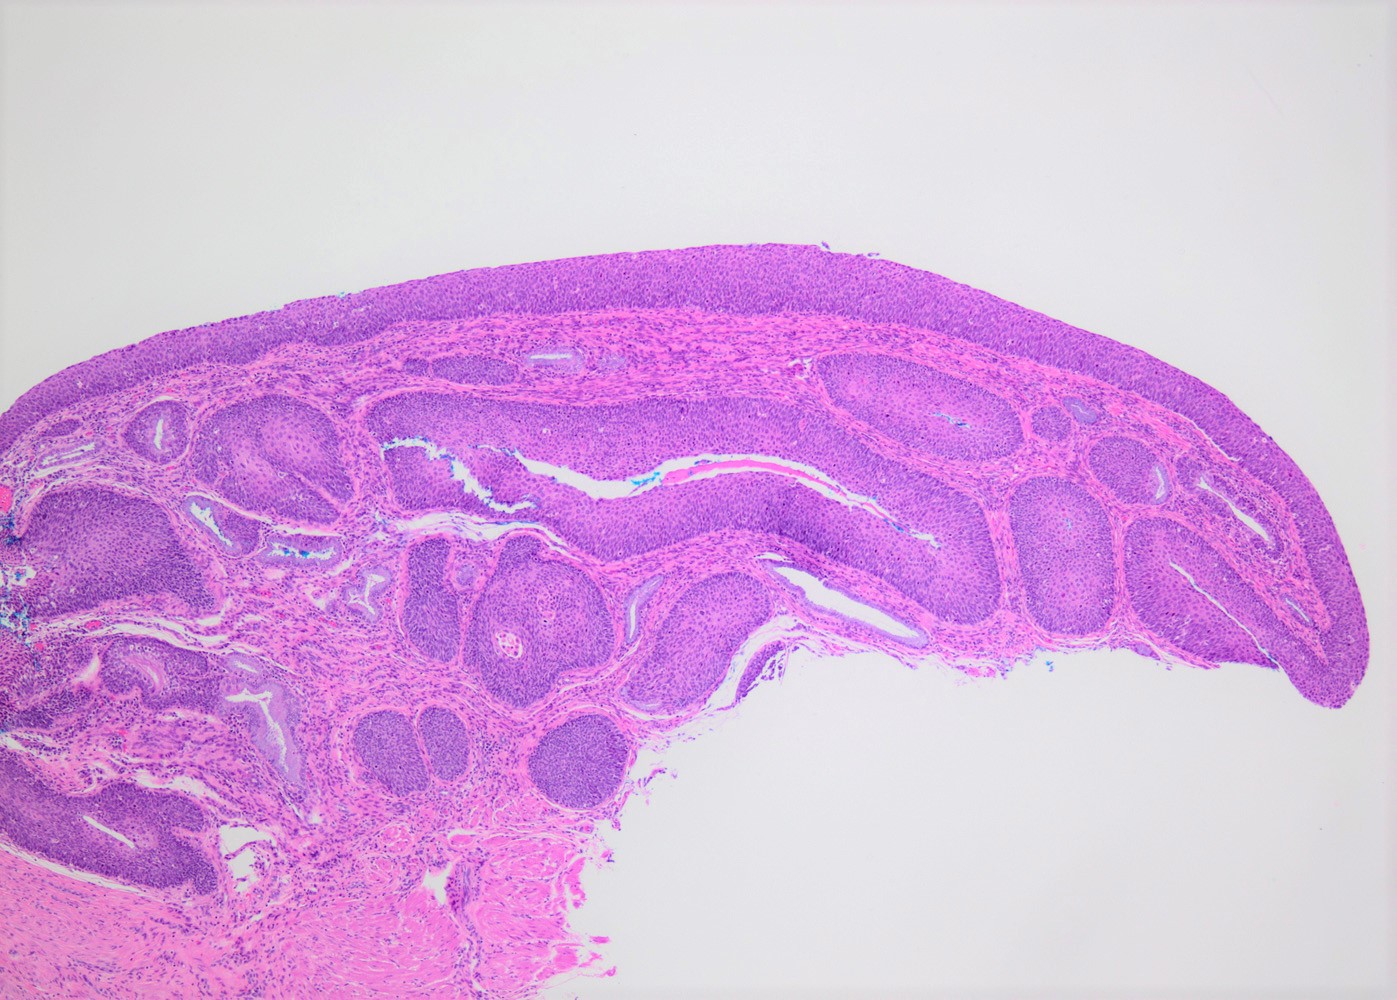

- Conventional / classic pattern: full thickness nuclear abnormalities (hyperchromasia, coarse chromatin, irregular nuclear contours and inconspicuous nucleoli), high N/C ratio in at least lower two - thirds of epithelium

- CIN II: cytoplasmic maturation in the upper third of mucosa

- CIN III: full thickness basal / parabasal type, no maturation difference across layers

- Increased mitotic activity with atypical mitoses

Microscopic (histologic) images

Contributed by Khaled J. Alkhateeb, M.B.B.S.